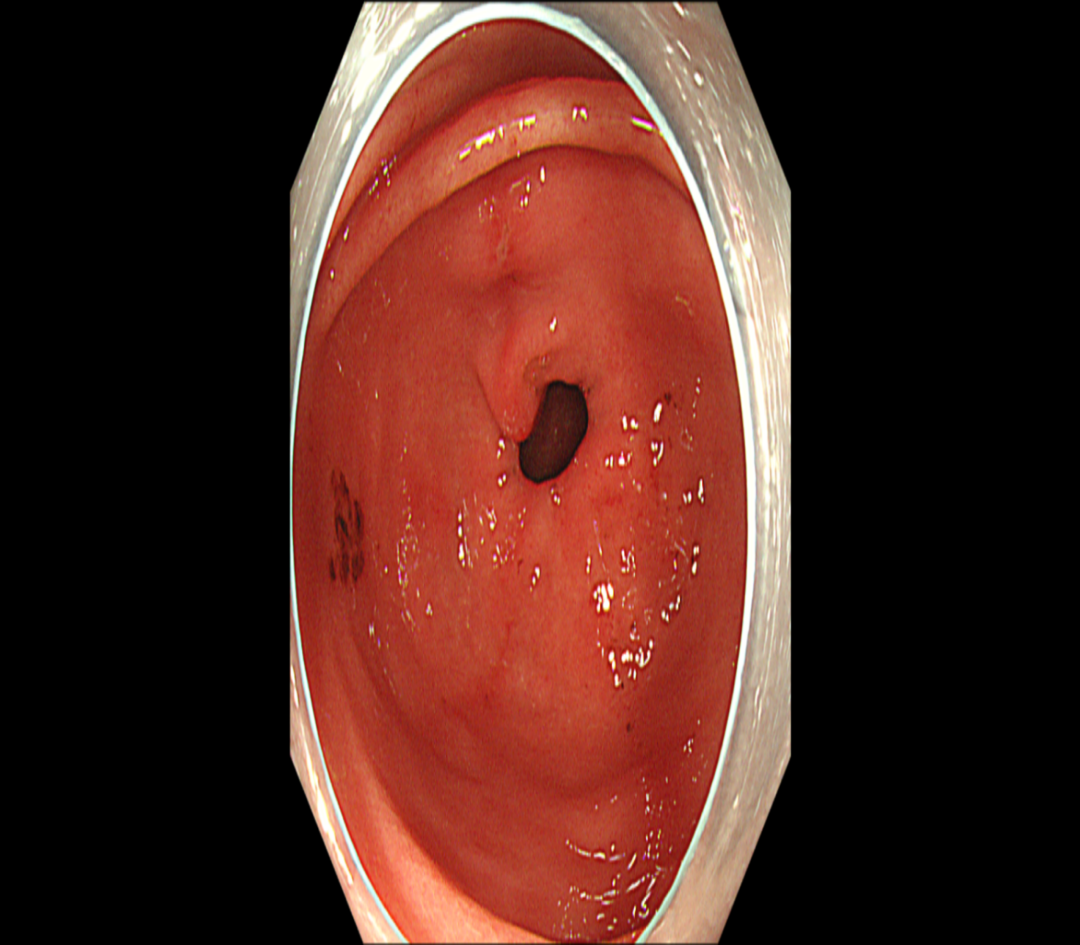

麻醉肠镜(图4

回肠末段未见异常;结直肠多发息肉(4枚CFP);内痔。

图4 肠镜示结肠息肉

肠镜病理

1、(回末黏膜活检组织)黏膜局灶性炎,伴淋巴滤泡形成。刚果红(-)。 2、(横结肠黏膜活检组织)符合增生性息肉。刚果红(-)。 3、(直肠黏膜活检组织)增生性息肉。刚果红(-)。